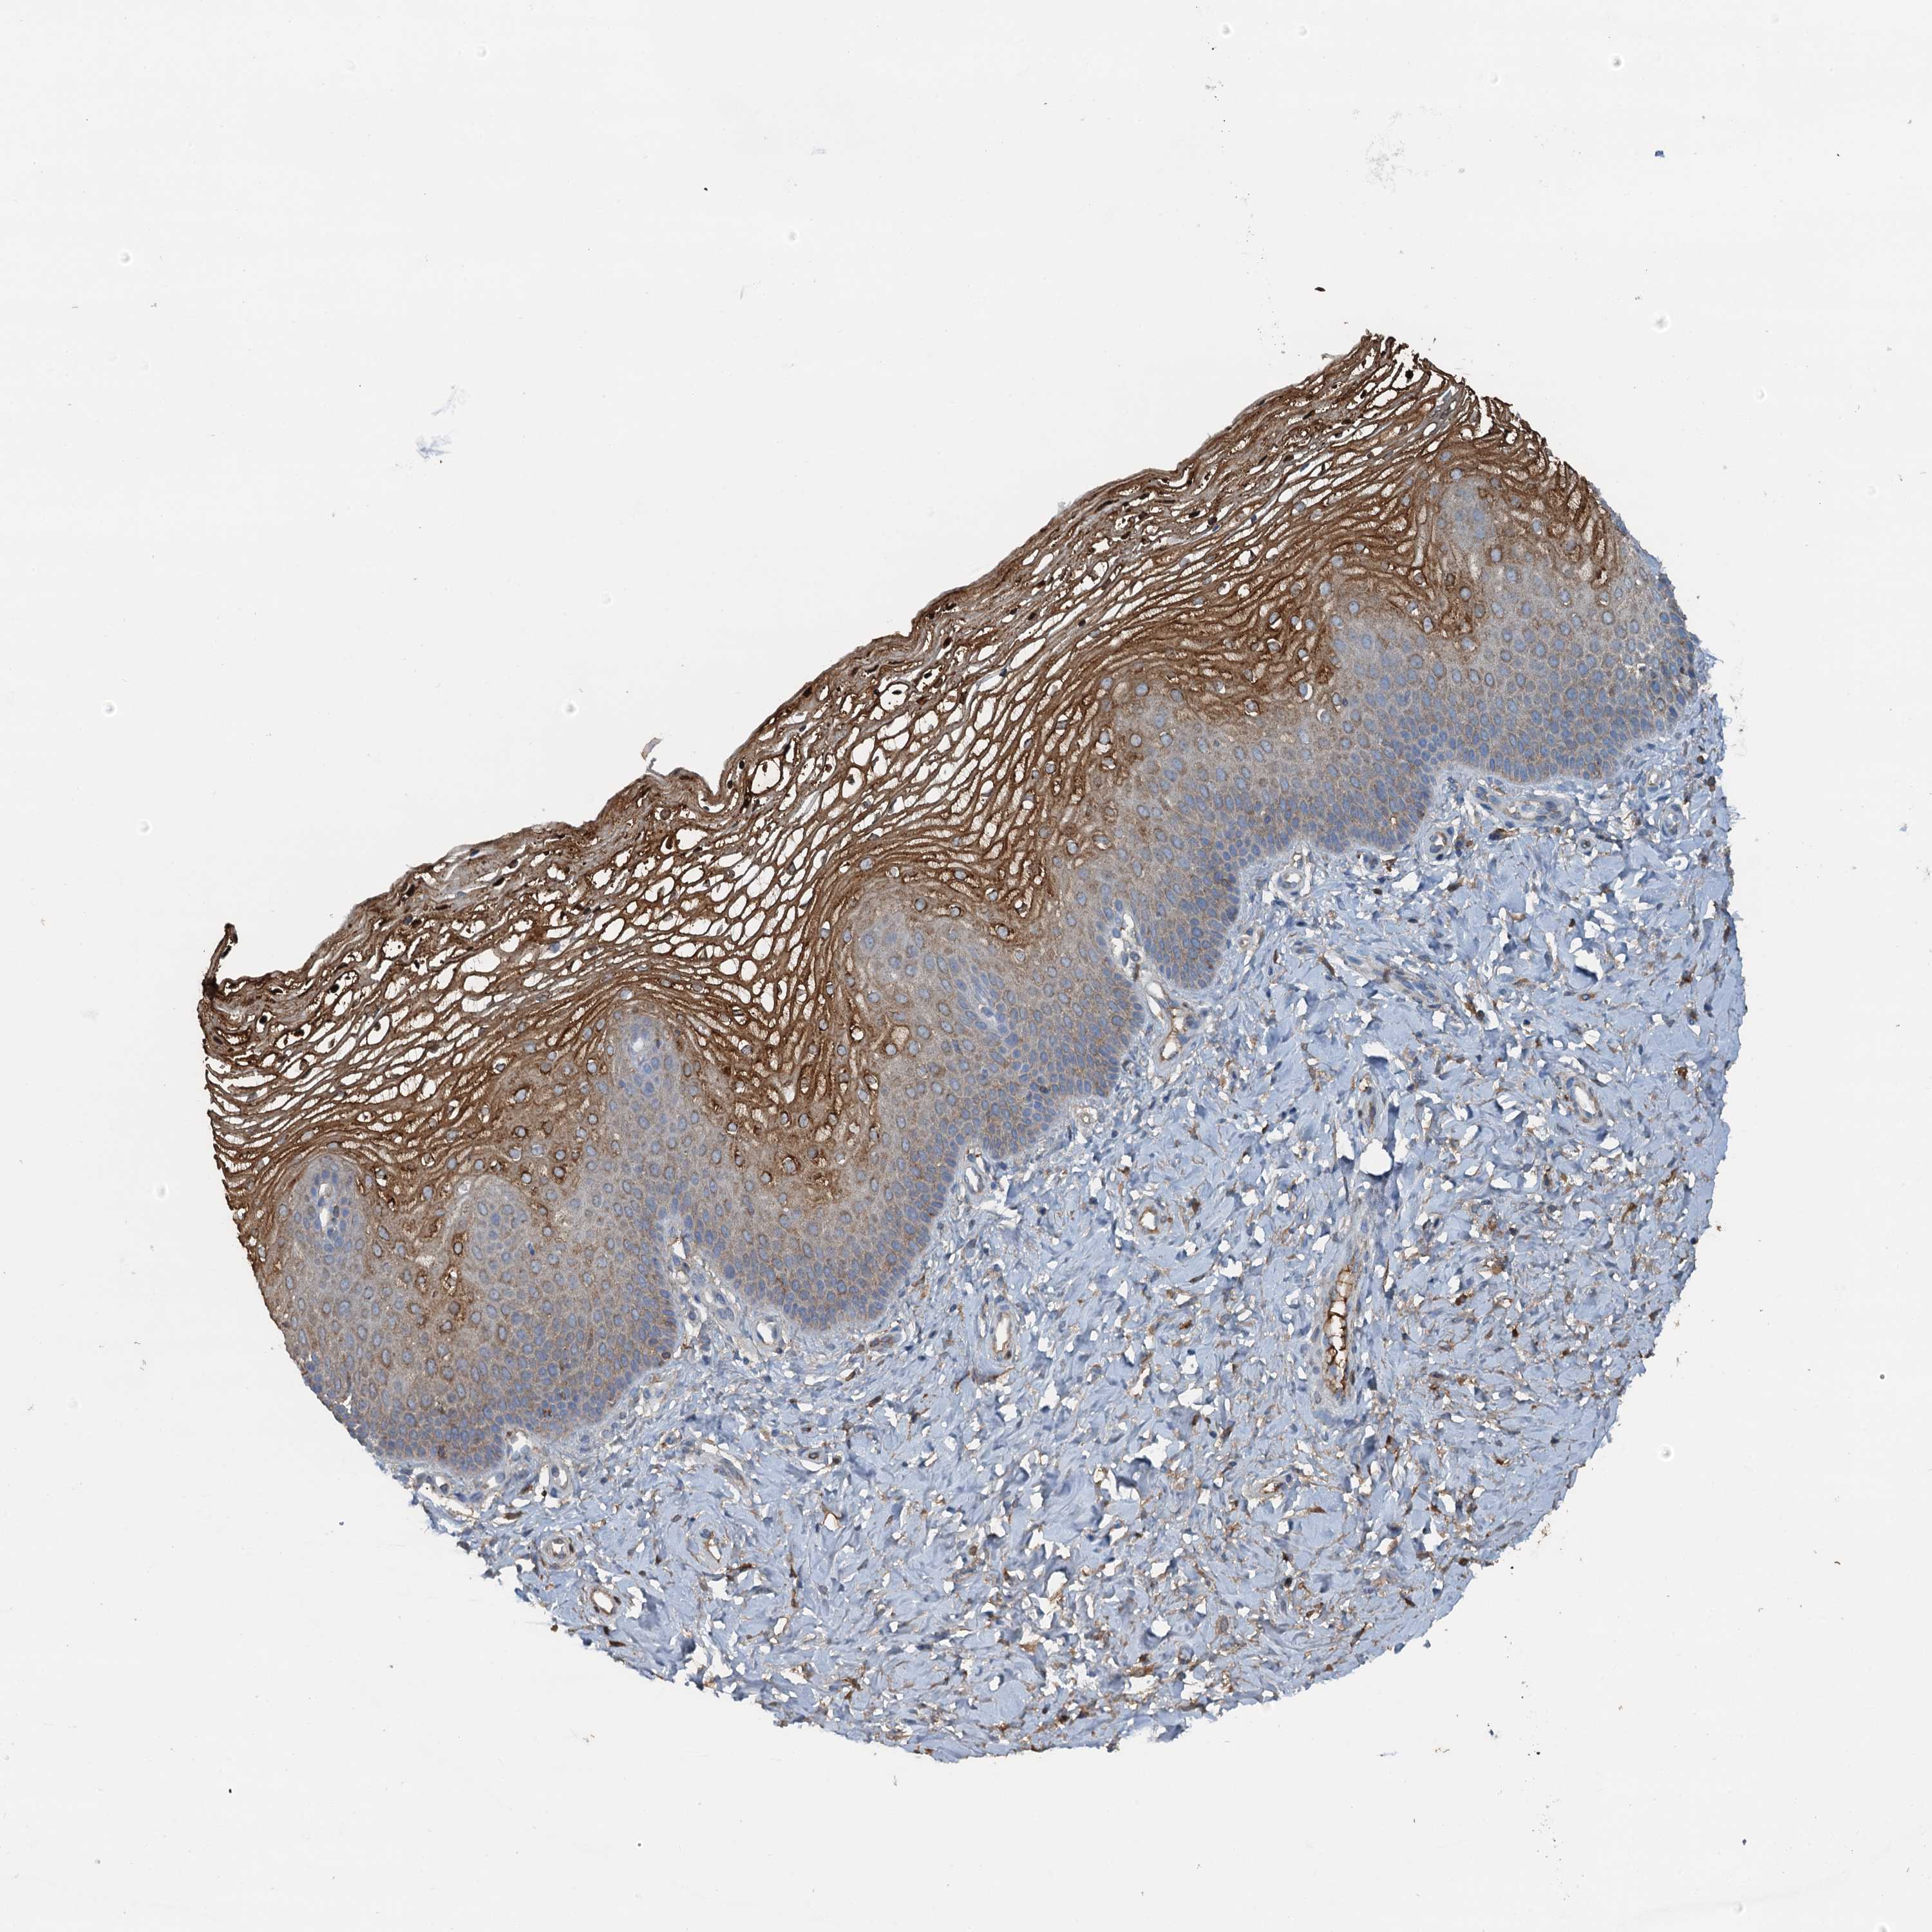

Antibody staining in the annotated cell types in the current human tissue is reported as not detected, low, medium, or high. This score is based on the staining intensity and fraction of stained cells.